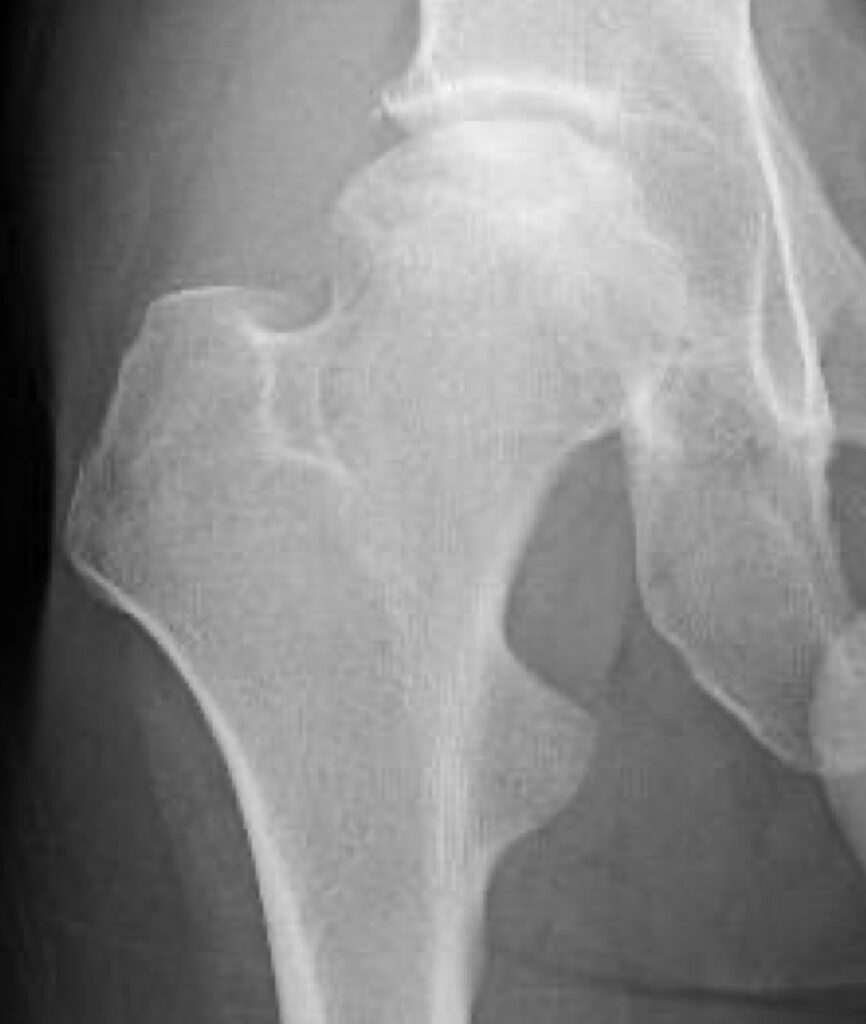

股関節の中心である大腿骨頭が壊死してつぶれるために痛みを生じる病気です。アルコールの多飲やステロイドの使用に関連しているとも言われていますが、いまだにはっきりしておらず国の難病に指定されています。骨頭の破壊が強ければ人工股関節置換術が必要になることがあります。

大腿骨頭壊死のレントゲン